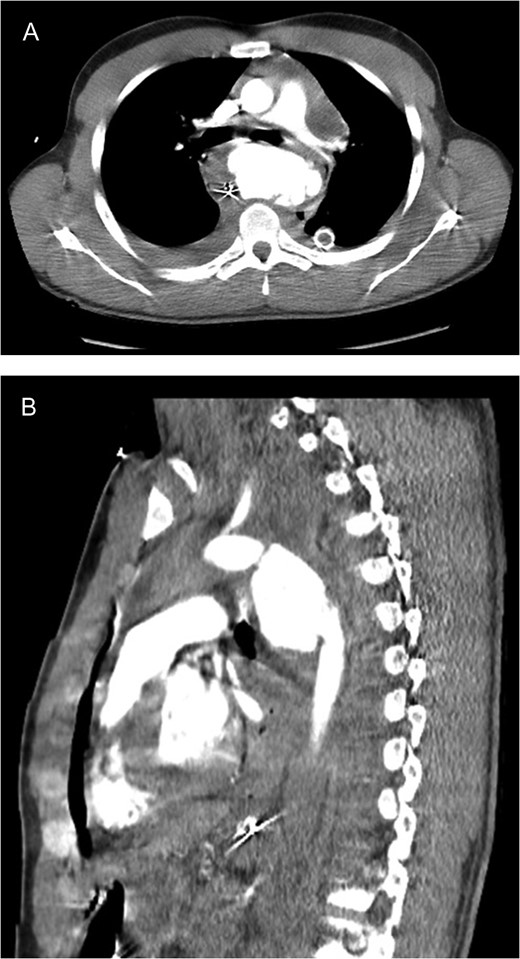

CT scan images (A axial; B sagittal) demonstrating aortic rupture with active contrast extravasation at the level of the proximal descending aorta just distal to the ductus on both axial and sagittal imaging.